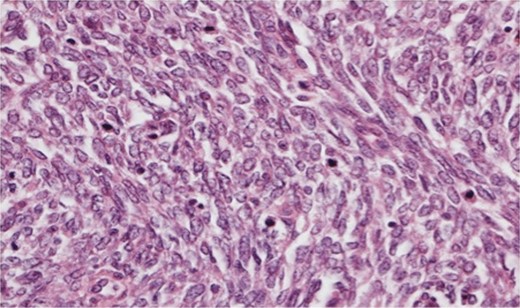

The histopathology demonstrated that the breast was partially replaced by a partly cystic and partly solid necrotic lesion. The cystic cavity contained blood clots. A microscopic examination showed an atypical undifferentiated spindle cell lesion with a fascicular architecture, pleomorphism and marked mitotic activity with areas of ulceration and necrosis (Figs 1 and 2). The initial set of immunostains performed showed that tumour cells were negative for cytokeratins (Fig. 3), S100 and LCA. The tumour cells showed diffuse and strong vimentin positivity (Fig. 4). Further immunocytochemical labelling showed weak expression of CD99, patchy strong expression of CD10 and patchy weak expression of smooth muscle actin. Cytokeratins (CAM 5.2) and EMA were expressed and there was no tumour-specific expression of CD34, desmin or myogenin. Fluorescent In-situ hybridization analysis failed to demonstrate evidence of a t(x:18) translocation using the LYS-SYT break apart probe. The diagnosis of a Grade 3 undifferentiated spindle cell sarcoma was made and although the tumour was reported to have a clear resection margin (5 mm) in most areas, the presence of necrosis and granulation tissue reaching the deep margin made the status of the margin uncertain.

Photomicrograph ×40 H&E; pleomorphic spindle cells in fascicles with several mitoses.